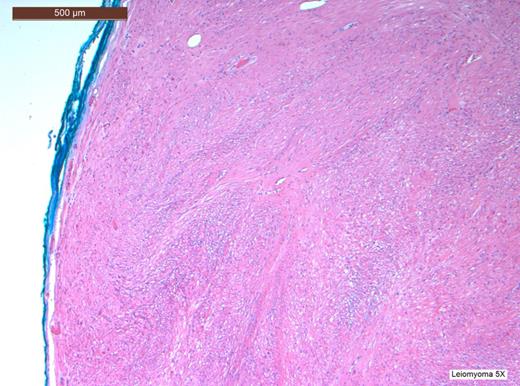

Histopathological analysis of the lesion, including immunohistochemical profiling, revealed a well-circumscribed nodular tumour composed of smooth muscle cells with eosinophilic cytoplasm and spindle-shaped nuclei. The cells were arranged in interlacing fascicles with evidence of perinuclear vacuoles using haematoxylin and eosin staining. There was no evidence of necrosis, mitosis or significant nuclear pleomorphism. The specimen was negative for CD117 staining, hence excluding the possibility of a gastrointestinal stromal tumour. It was also negative for S100. However, stain was positive for smooth muscle actin (SMA) and desmin, which confirmed that specimen was of muscular origin. The histology therefore identified the lesion as a leiomyoma (Figs 2–6).

H&E stain at low power view revealing a tumour with a well-circumscribed edge with fascicles of spindle-shaped cells.